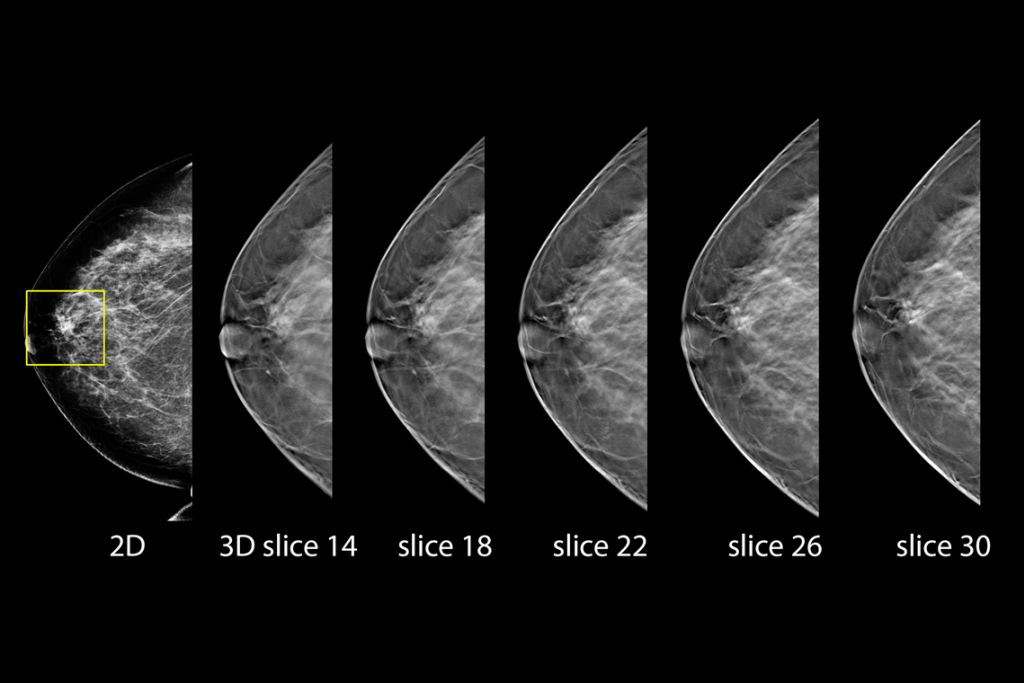

Kliniske billeder fra mammografi af et bryst med en mistænkelig læsion

Kliniske billeder fra mammografi af et bryst